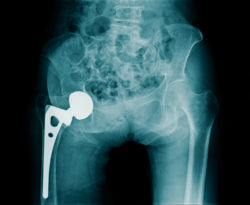

Like other metal-on-metal hip implants, DePuy ASR hip implants were marketed to be superior choices for patients needing a hip prosthetic. When metal-on-metal hip implants were first released into the market, they were thought to be overtly superior to plastic or ceramic models.

So what makes metal-on-metal hip implants so problematic? Initially, they were invented as an efficient alternative to their ceramic and plastic counterparts. Believed to last longer and possess better durability, they were thought to be all-around superior at the time. However, not long after metal hip implants were released, problems with the metal-on-metal design were reported.

It was soon discovered that, as the metal ball-and-socket joints rubbed together as the patient moved, metal particles started rubbing off from the device and slipped into the patient’s bloodstream, leading to metal poisoning, pain, implant loosening, device failure, and revision surgery. This often can compound the patient’s condition and cause them to suffer a multitude of other problems including: